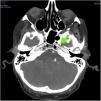

This is the case of a hospitalized patient whose jugular central catheter is removed while sitting on a couch prior to his hospitalization. A few seconds later, the patient develops dissociative disorder, hypokinesia, and acute respiratory failure. A stroke is suspected. The simple cranial CT scan and coronary computed tomography angiography (CCTA) performed reveal no signs of acute ischemia or major cerebral vessel occlusion, but the presence of numerous aerial bubbles at right jugular vein, cerebral cavernous sinuses, extra-axial intracranial sinuses, and a few intra-medulla oblongata bubbles at clivus level (Figs. 1–3). All signs of venous air embolism. This is a rare complication associated with central venous catheters. However, proper management of these is important regarding insertion, maintenance, and removal both at the intensive care unit and hospital ward settings to avoid complications.